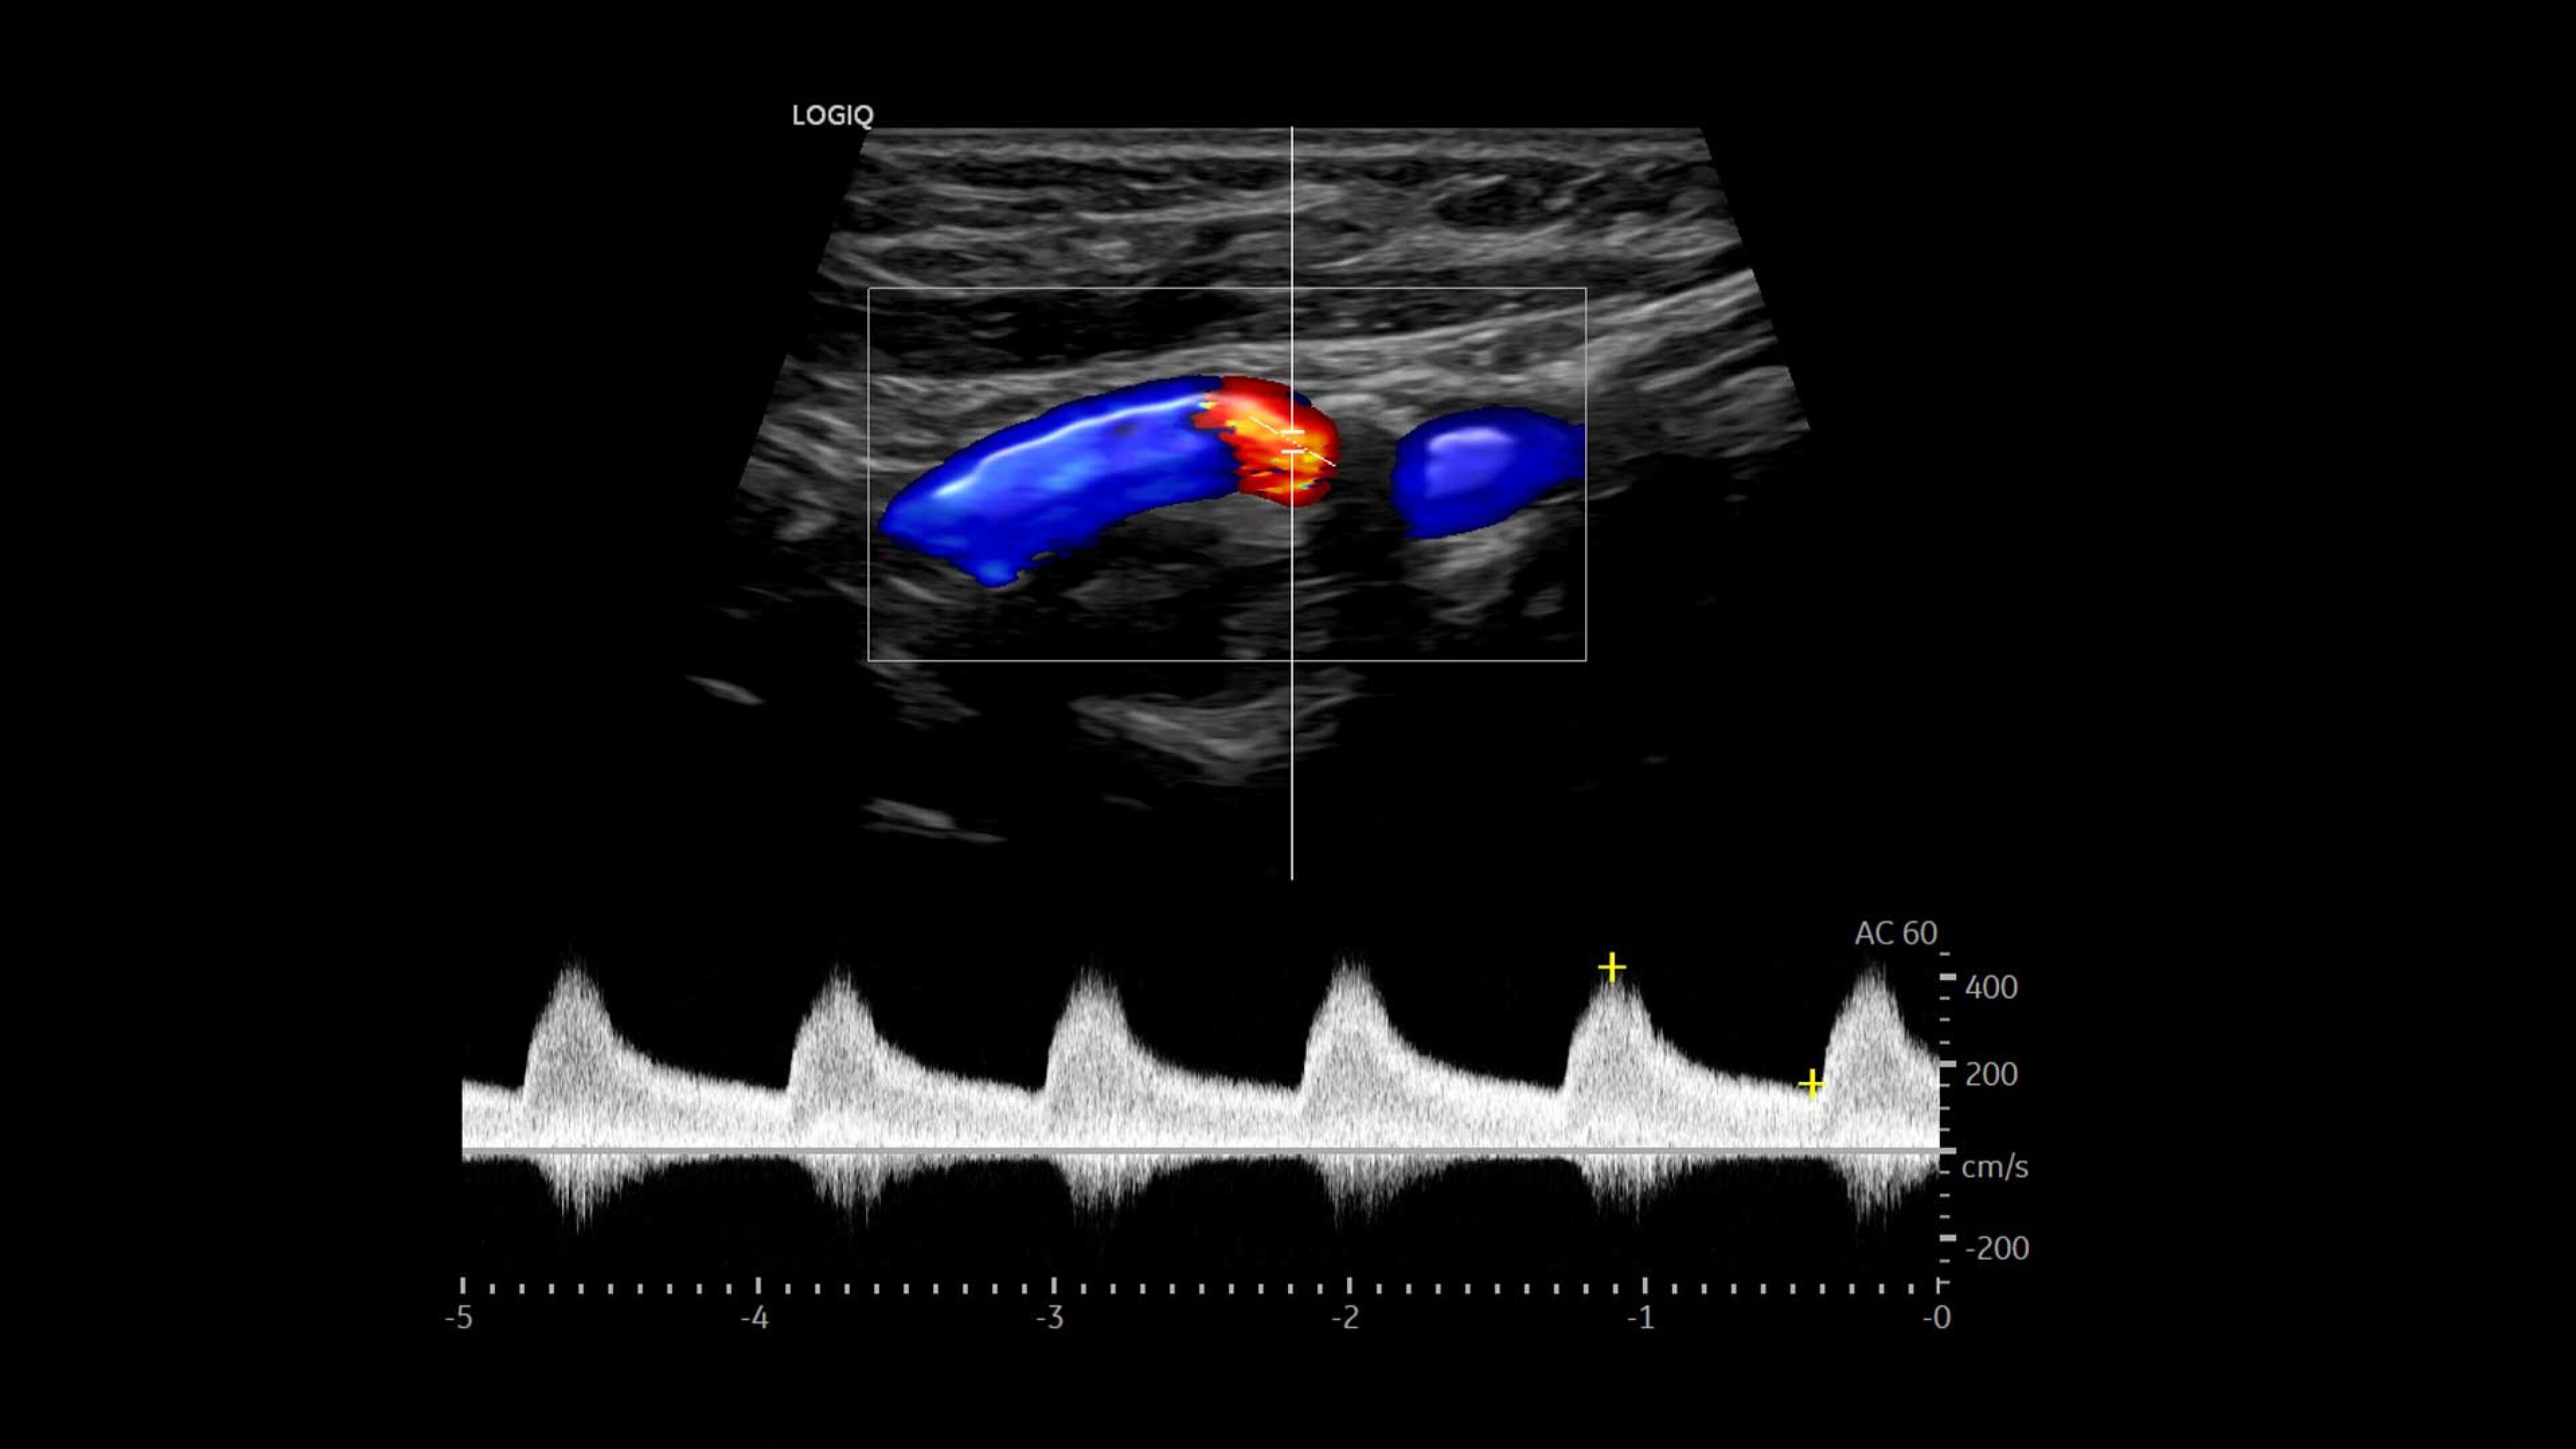

LOGIQ Totus™ Ultrasound

Multi-purpose excellence. Introducing LOGIQ Totus – a head-to-toe, comprehensive ultrasound experience that redefines your expectations.

The LOGIQ Totus™ system is a portable, multi‑purpose, comprehensive solution that combines AI‑powered workflow and decision‑support tools to enhance efficiency and versatility, while its high‑quality imaging supports head‑to‑toe diagnostic confidence.

• Rely on cSound™ Architecture, which delivers exceptional image quality and uniformity

• Leverage a wide range of transducers, including XDclear™, which produces high resolution images covering head-to-toe applications across clinical specialties or care areas

• Address clinically challenging cases with advanced tools such as 2D Shear Wave Elastography, Ultrasound-Guided Attenuation Parameter (UGAP), and Volume Navigation